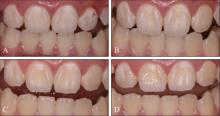

谷希, 张立亚, 陈瑞雪, 等. 渗透树脂修复磨牙-切牙矿化不全的美学效果评价[J]. 口腔疾病防治, 2021, 29(10): 689-694.

|

Gu X, Zhang LY, Chen RX, et al. Esthetic evaluation of resin infiltration for the treatment of molar-incisor hypomineralization[J]. J Prevent Treat Stomatol Dis, 2021, 29(10): 689-694.